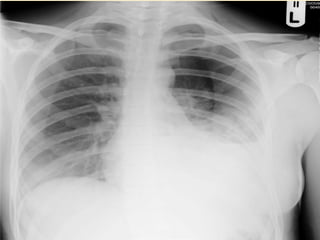

BREATHING & VENTILATION

“ Look , feel , palpate and listen “ for

Tension pneumothorax

Open pneumothorax

Severe flail chest

Resuscitation

Oxygenation : FiO2 > 0.85

High pressure pneumothorax causing cardiovascular

compromised status

* chest injury

* dyspnea & tachypnea

* distended neck vein

* deviated trachea

* hypotension

* tympanic on percussion

* absent breath sound

Abnormal connection between pleural cavity and

atmosphere causing inability to ventilate the

lungs

Resuscitation : three-sided dressing

: ICD

: Oxygenation

Segmental separation of chest wall causing inability to

breath and ventilate the lungs

* paradoxical movement

* decreased breath sound

Resuscitation : intubation & respirator

: pain control

: breathing exercise

MASSIVE HEMOTHORAX

● Systemic / pulmonary

vessel disruption

● > 1500 mL blood loss

● Flat vs. distended

neck veins

● Shock with no breath

sounds and/or

percussion dullness